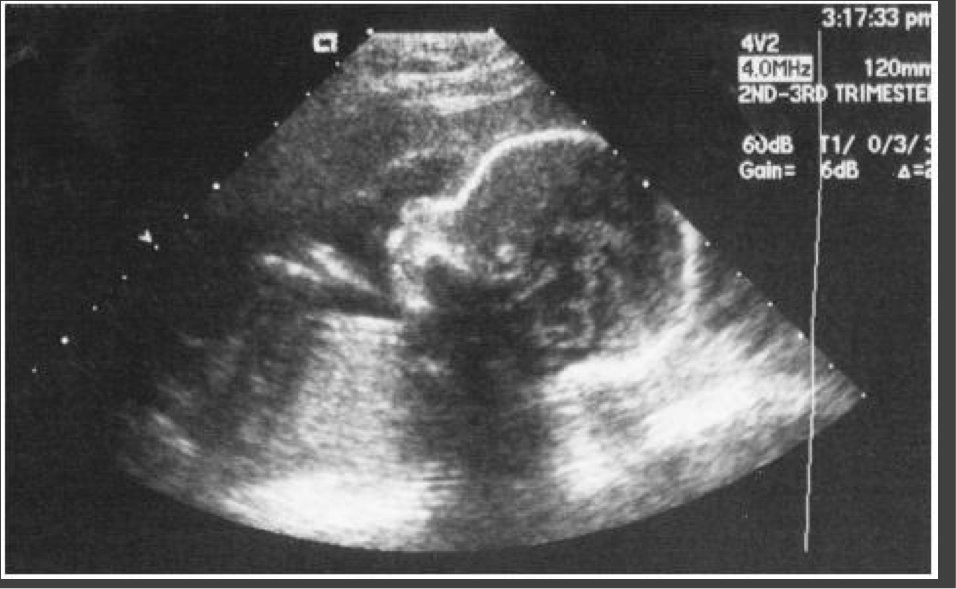

Fetal U/S